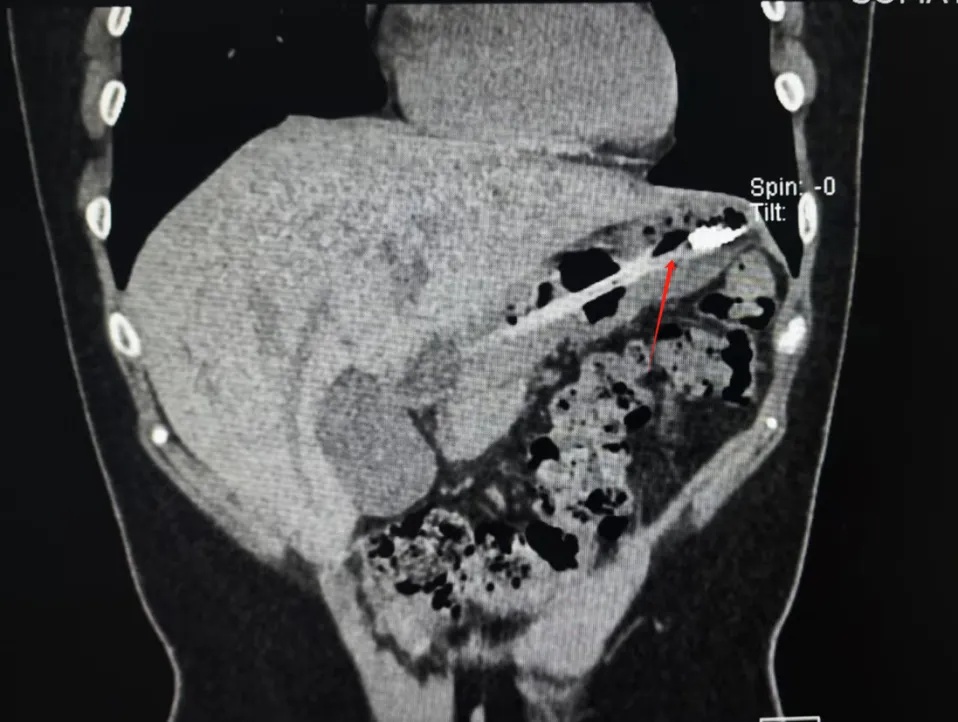

而四川成都女生小李

为了缓解因暴饮暴食带来的

胃部不适和长胖焦虑

竟然选择用一次性牙刷

作为催吐工具

结果手打滑,18cm长牙刷

顺着咽喉直接滑了下去

幸运的是

由于小李就医及时

牙刷最终被顺利取出

并未对胃壁造成严重的损伤